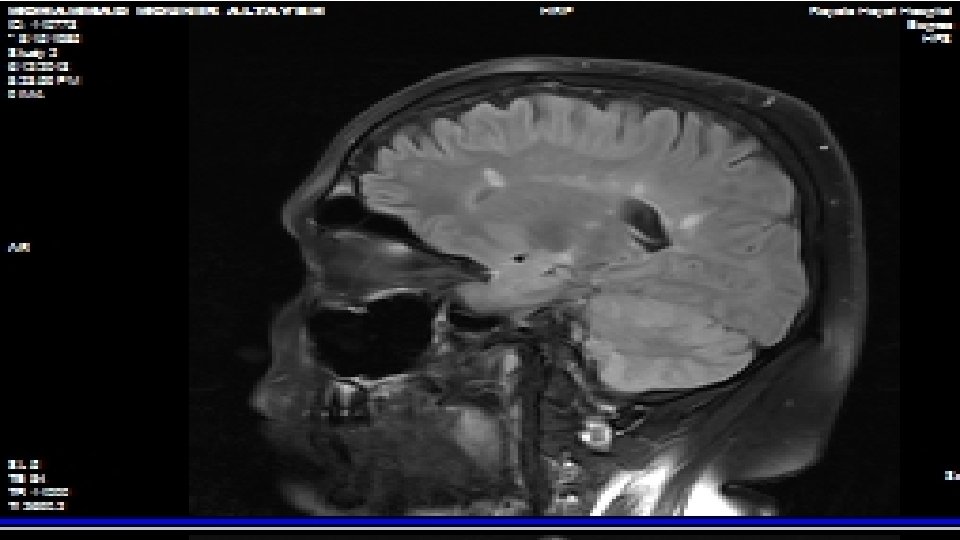

What tests may be used to help confirm the diagnosis? 1 -Magnetic resonance imaging (MRI) 2 -Visual evoked potentials (VEP) 3 -Lumbar puncture

Mc. Donald Diagnostic Criteria MRI-High Specificity & Sensitivity for MS Typical MS demyelinating lesions meeting at least 3 of the following 4 criteria: 1 -At least 1 Gd lesion or at least 9 T 2 lesions 2 -At least one infratentorial lesion 3 -At least one juxtacortical lesion 4 -At least 3 periventricular lesions

Mc. Donald Diagnostic Criteria MRI-Dissemination in Time If the first MRI is performed 3 months after the clinical event, 1 of the 2 below must be found: > 1 Gd lesion not at site of original attack; or MRI 3 months later showing a new T 2 or Gd lesion

Case : MRI Brain